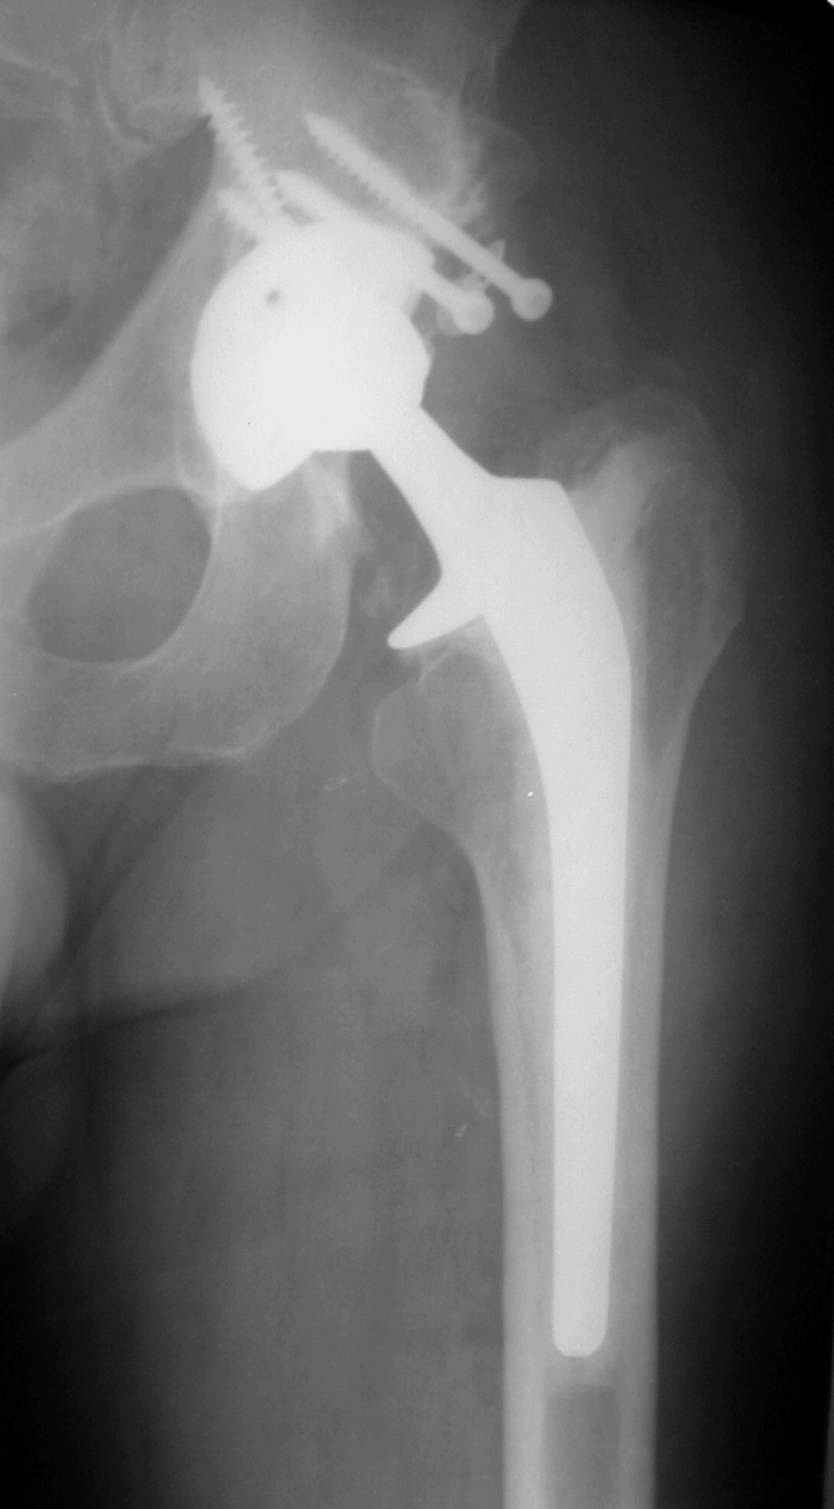

В институте совместно с фирмой Зиммер достаточно регулярно (практически ежемесячно) проводятся 2-х недельные циклы по различным вопросам эндопротезирования. Если есть возможность и желание, мы готовы поделиться с Вами нашим опытом, тем более есть что показать и что обсудить - в настоящее время ежедневно выполняется от 6 до 10 эндопротезирований коленного и тазобедренного сустава. В качестве примеров хочу показать 2 наблюдения, через 1 год и 5 лет после операции

1 год

5 лет